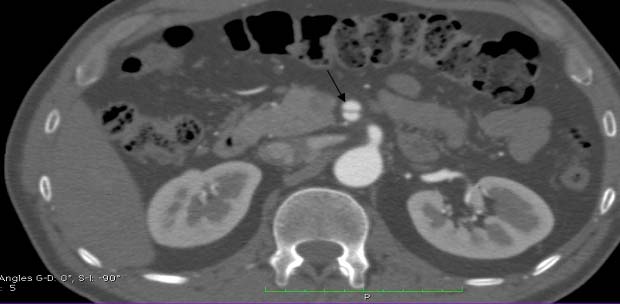

Dissection of SMA was extending for approximately 1.8cm, accompanied by contrast accumulation in the wall due to ulceration in the proximal part of the artery. SMA was visualized as 60% narrowed because of the dissection [Table/Fig-4,5 and 6]. Inferior Mesenteric Artery (IMA) and renal arteries were normal. Conservative treatment was the method of choice. It was based on anticoagulation, pain and hypertension control. His abdominal pain resolved in 2 days. The patient was discharged home with warfarin and aspirin. Follow-up CT scan at 3 and 6 months demonstrated that the dissections and aneurysmal dilatation were both stable. The patient was continuing to do well on his 15 month clinical follow-up. Further follow-up CT examinations were planned.

Axial contrast enhanced computed tomographic scan through the upper abdomen shows an intimal flap (arrow) in the SMA This finding is consistent with SMA dissection.